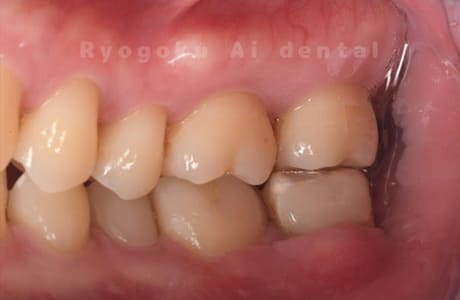

Case27

-

重度カリエス

歯牙移植咬合面術前 -

移植する親知らず

歯牙移植術直後咬合面

歯牙移植術後咬合面

歯牙移植術前側面

歯牙移植術中側面

歯牙移植術後側面

部分矯正術前咬合面

部分矯正術中咬合面

部分矯正術後咬合面

部分矯正術前側面

部分矯正術中側面

部分矯正術後側面

- 原因

- 重度カリエス

- 治療内容

- 自家歯牙移植、部分矯正

- 治療費用

- 220,000円(移植費用)

110,000円(部分矯正費用)

虫歯が大きく、保存不可能となった歯を上の親知らずと交換する自家歯牙移植を行いました。移植歯が小ぶりであったため、部分矯正を行い問題なく噛み合い、経過良好です。

<リスク・副作用>

治療後、痛みや違和感、出血、腫れなどが出る事があります。喫煙者、糖尿病などの方の場合、歯が生着しない場合があります。